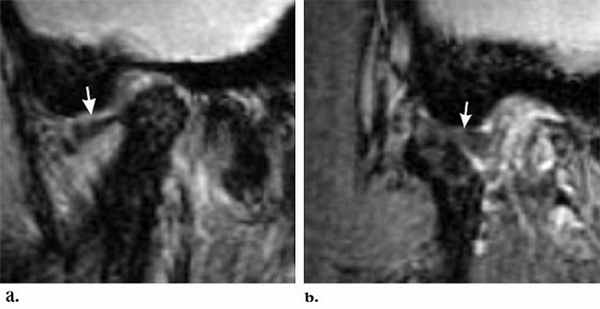

Фиксированный (невправляемый) вывих.

А. Рот закрыт. Переднее смещение диска.

Б. Рот открыт. Диск продолжает оставаться смещенным.